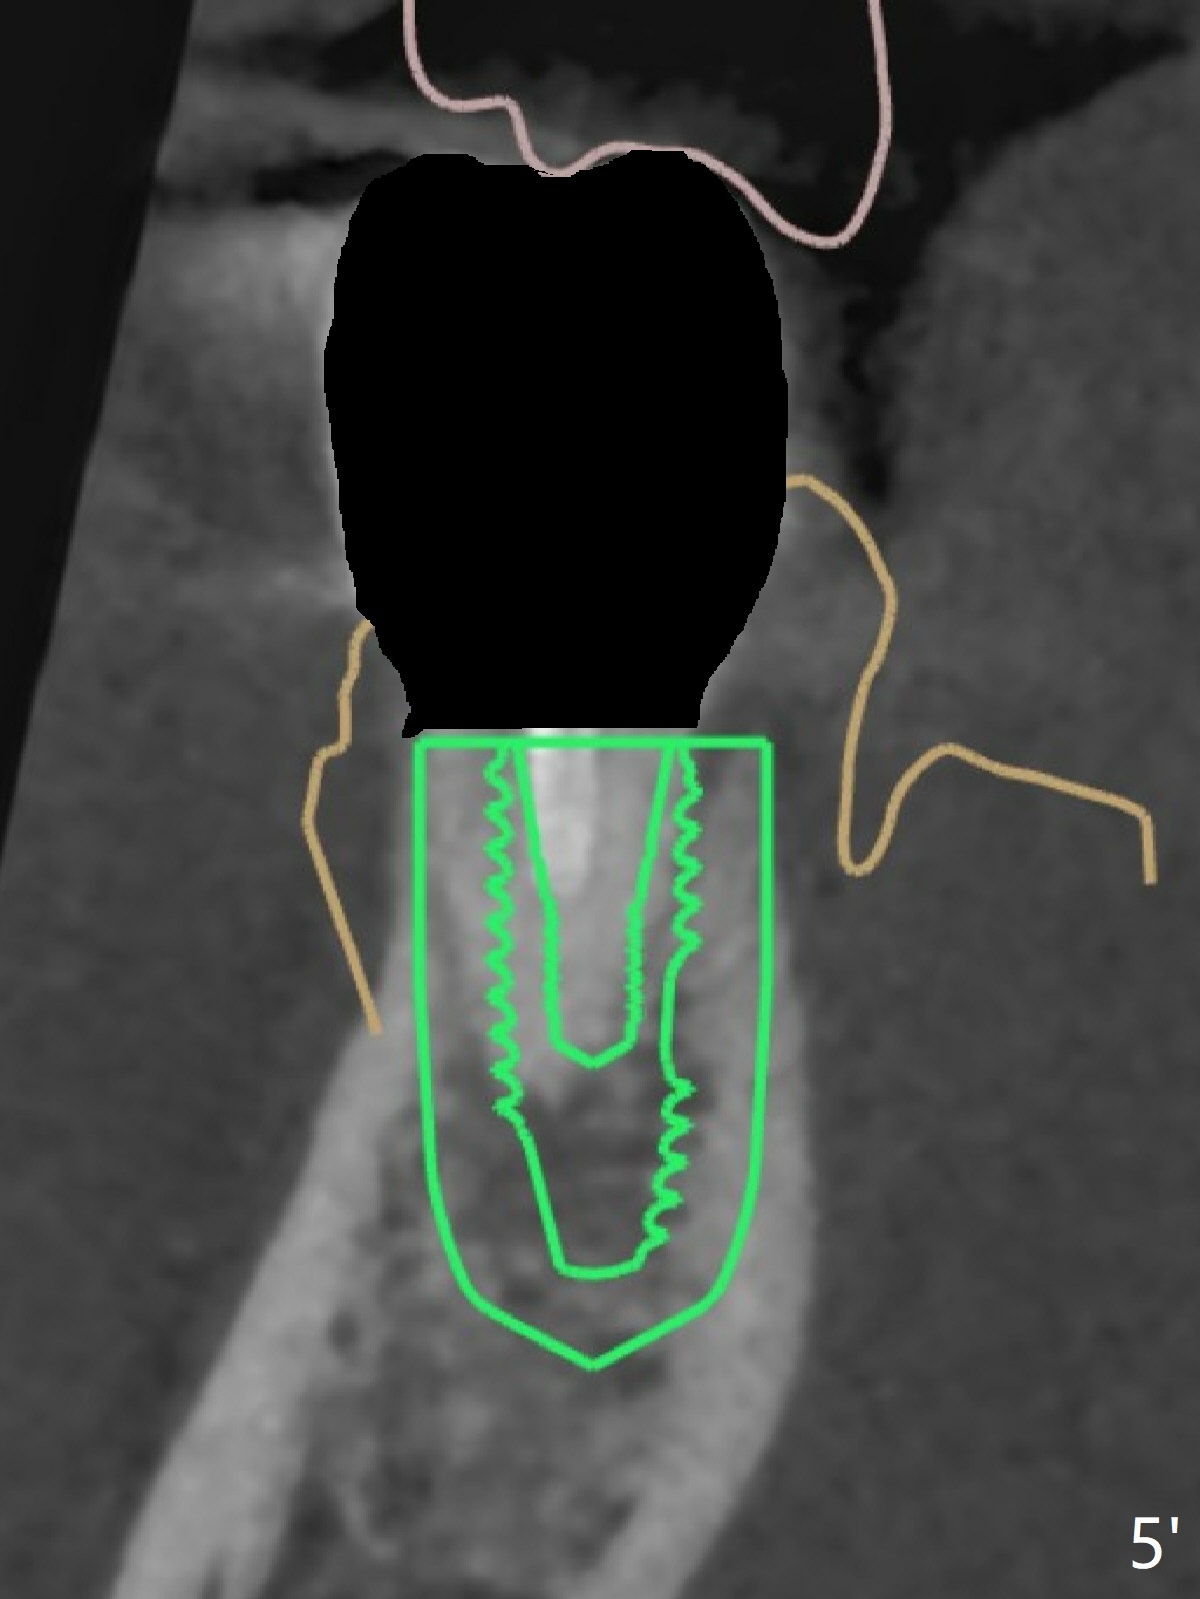

A 42-year-old man has been our patient for 3-4 years (Fig.1). An asymptomatic fistula develops lingual to the tooth #21 (Fig.2). An oblique fracture line appears to be next to a post (Fig.3 ^). A 3.5x11.5 mm implant seems to be able to be placed immediately lingual to the thick lingual plate with guide (Fig.4 L). No buccal deviation will occur with sufficient buccal gap. Design of an immediate implant at #21 (coronal section, Fig.5). In fact the root remains in place first (i.e., extract the crown first, Fig.5'). When osteotomy is done with the last drill 4x11.5 mm, there will be no deviation because of even counteraction between the buccal root and the lingual plate (Fig.6'). Then the root will be removed. But the 4.5x11.5 mm implant may be deviated buccal because of implant engagement into the lingual plate without buccal counteraction. Therefore, a 4x13 mm implant will be placed following 3.5x13 mm (last) drill. The implant is placed between the mesial and distal walls (Fig.7 sagittal section).